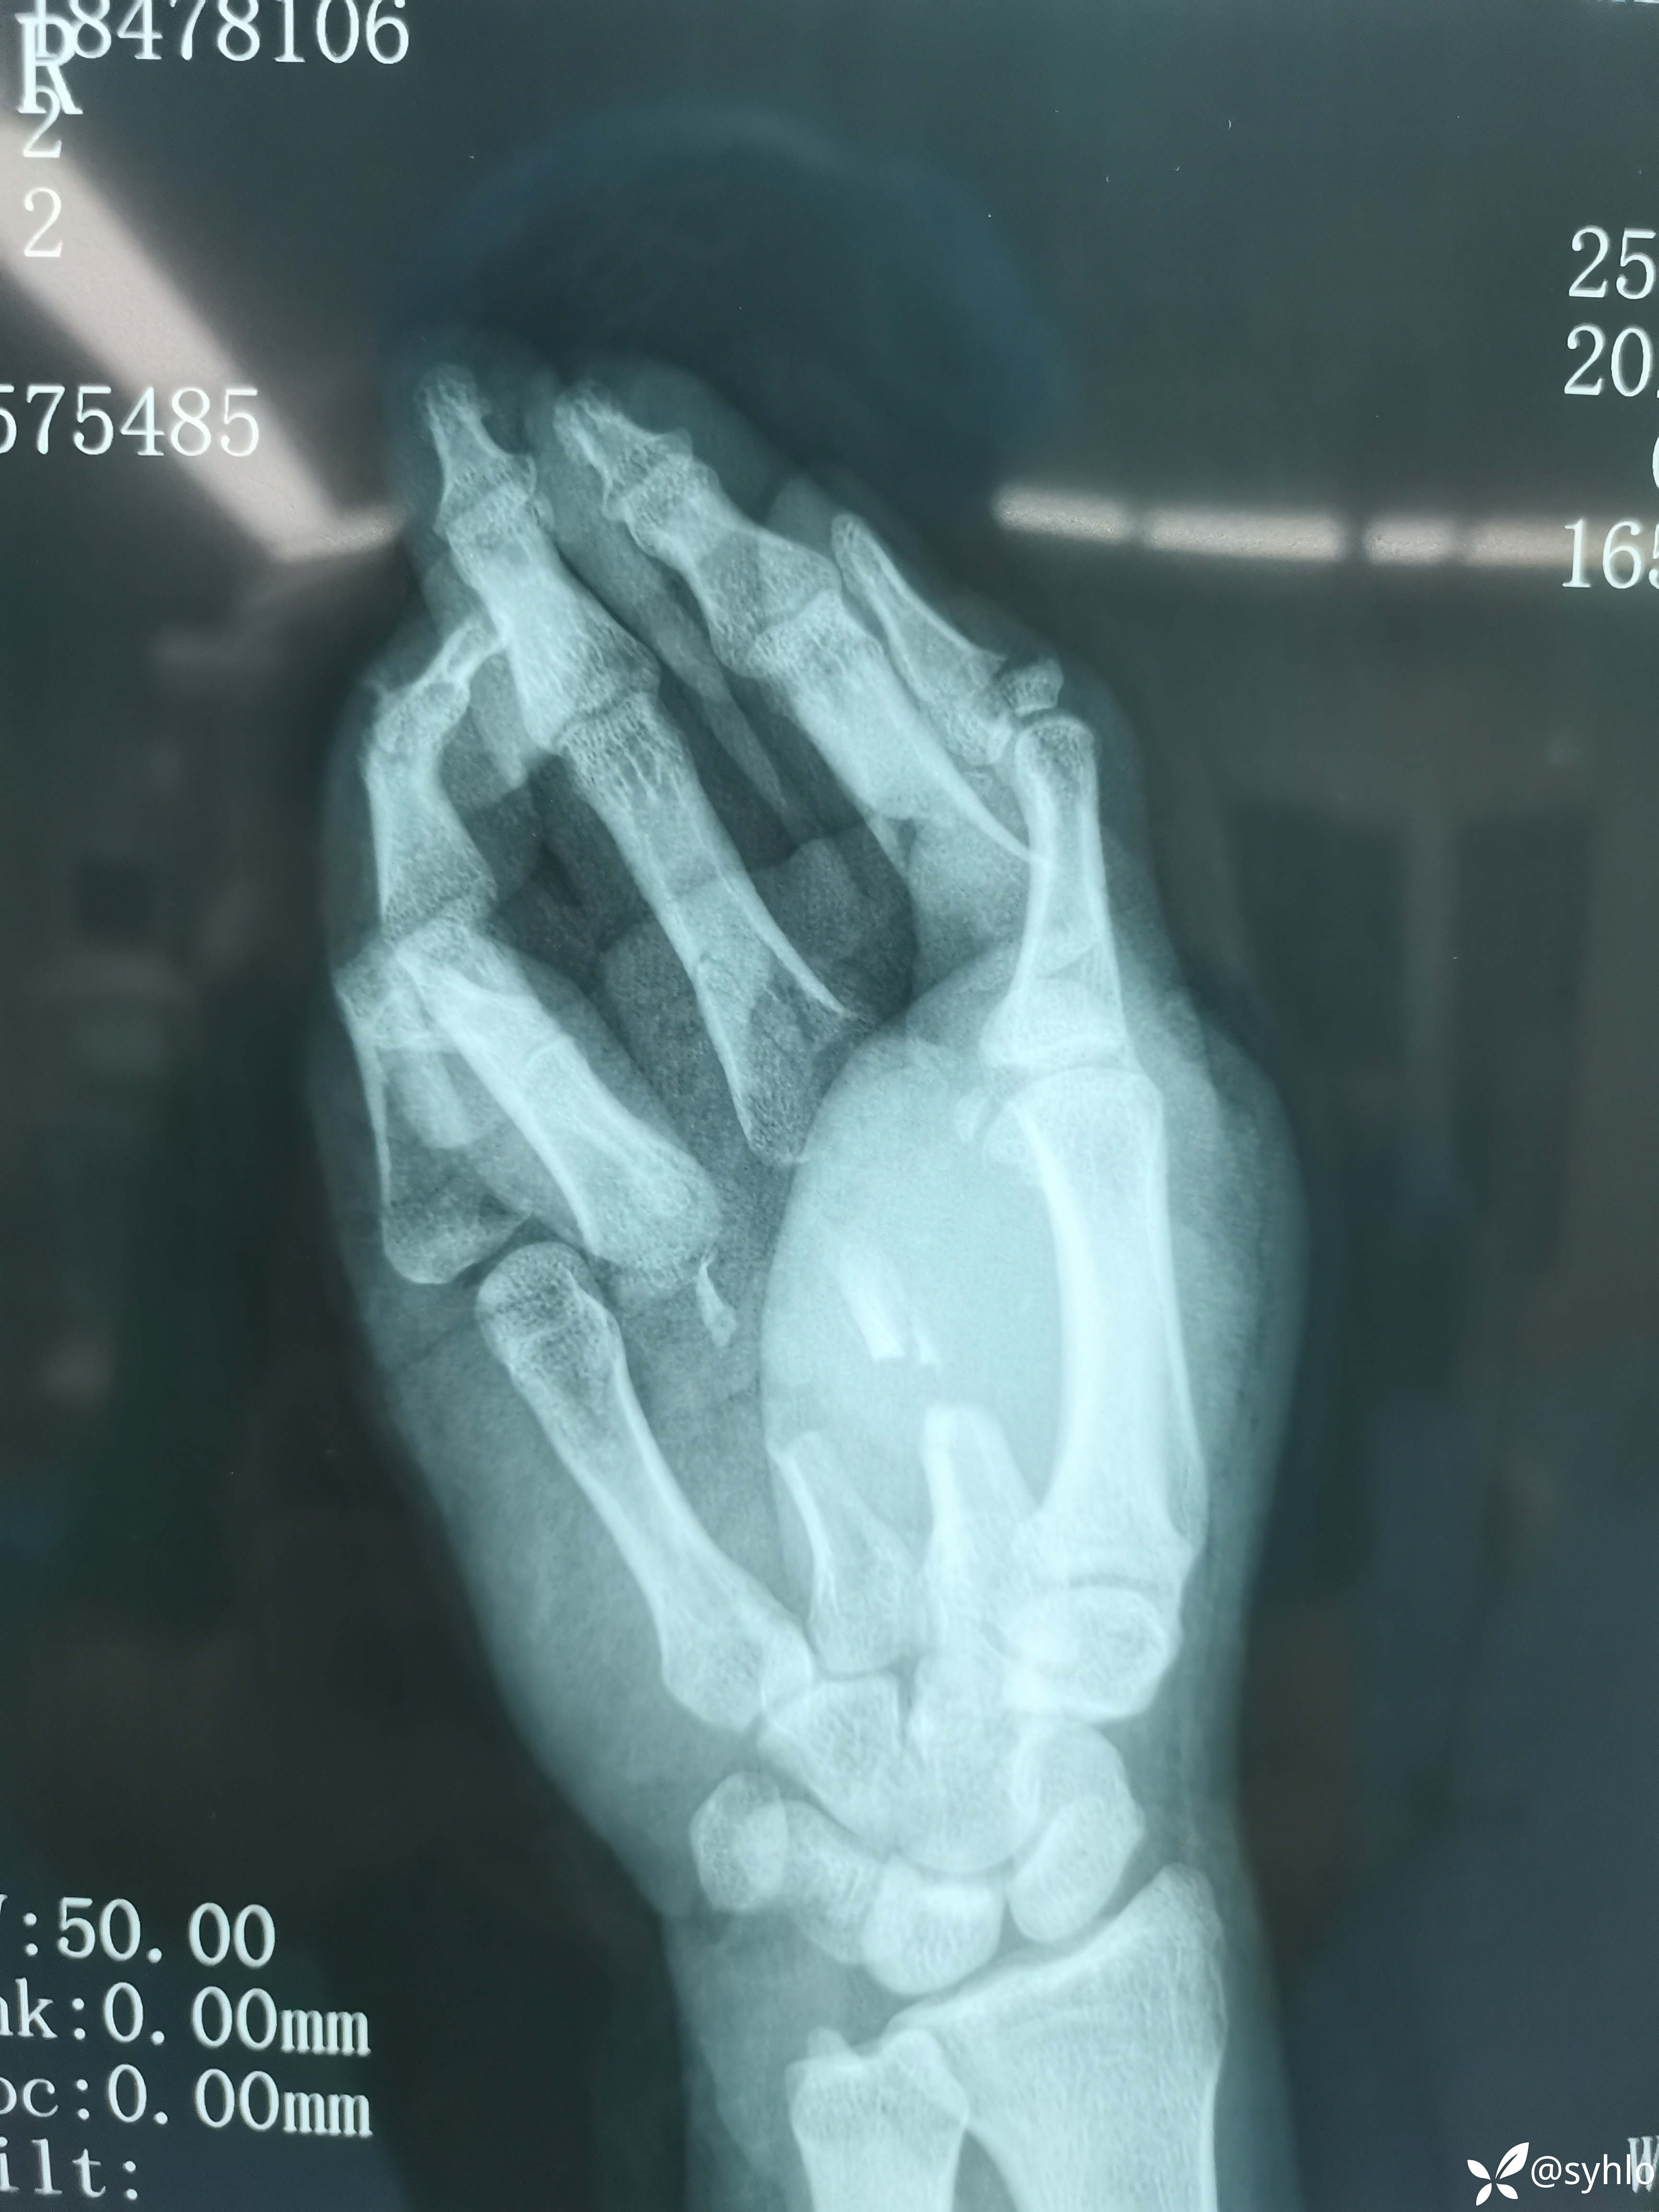

机器搅伤右上肢,缅甸籍贯在中国打工,家庭十分困难,多地辗转建议转省级医院治疗,家庭困难不愿意转。开放性肱骨,尺桡骨,掌骨骨折伴皮肤大面积撕脱。急诊清创外固定架+VSD负压吸引